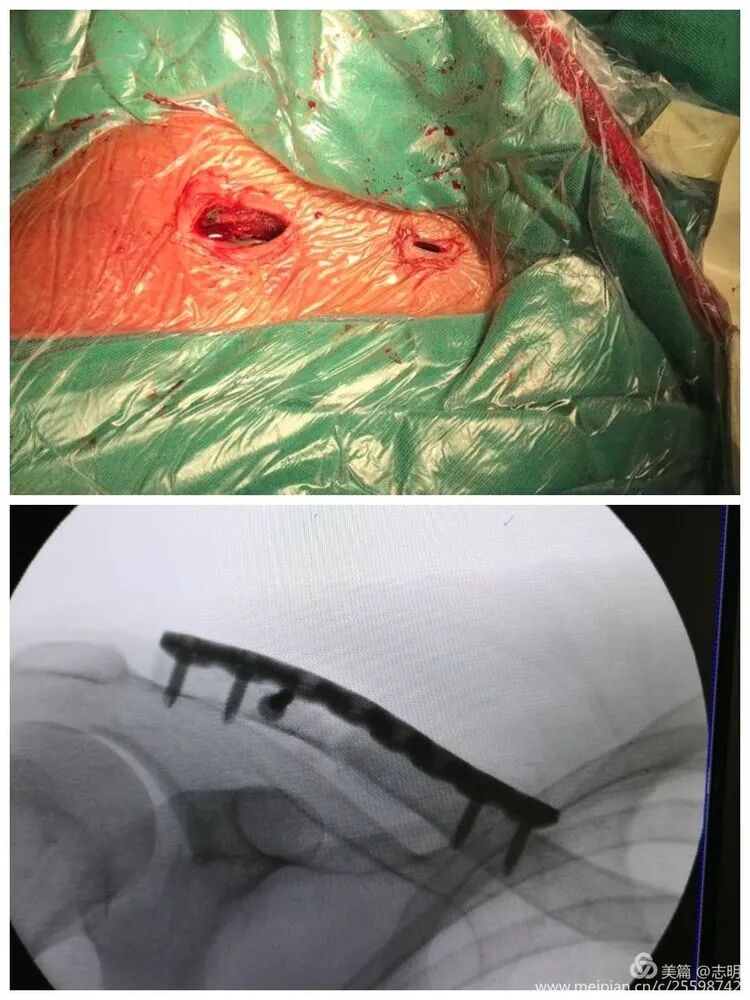

Subcutaneous Tunnel Creation

- Initial Dissection: Through each planned incision, carefully dissect down to the clavicle using blunt techniques, primarily. It is paramount to identify and meticulously protect the branches of the supraclavicular nerves within the subcutaneous tissue. Subplatysmal dissection is typically maintained.

- Tunneling Technique: A specialized MIPO tunnelizer, a blunt periosteal elevator, or a curved clamp is used to create a subcutaneous tunnel directly over the superior aspect of the clavicle, connecting the two incisions. The tunnel should be precisely wide enough to allow the unimpeded passage of the plate. The fundamental principle here is to remain directly on the superior cortical surface of the clavicle while avoiding any unnecessary or extensive periosteal stripping. This critical step preserves the vital surrounding soft tissue envelope and its associated blood supply, which is crucial for promoting robust biological fracture healing.

(Image likely illustrating an instrument used for tunneling or manipulating fragments percutaneously).

(Clinical image showing surgeon's hands manipulating the shoulder, likely assisting in reduction).

- Temporary Fixation: Once a satisfactory reduction is achieved, it must be temporarily secured prior to plate application. Percutaneous Kirschner wires (K-wires) are commonly used for this purpose. The seed content states: "对于长斜形等易临时固定的骨折,可经皮钻入1.5mm克氏针维持复位" (For long oblique fractures and others easily temporarily fixed, 1.5mm Kirschner wires can be percutaneously drilled to maintain reduction). Ensure that the K-wires are placed in a manner that does not impede subsequent plate placement or screw trajectory.